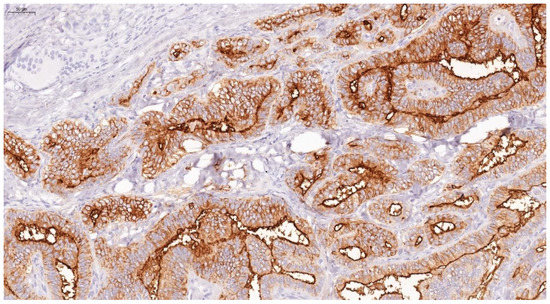

4.1. Immunohistochemical Results

| Thyroid Carcinoma | Papillary carcinoma | 80.49 | 0.012 | 68.28 | 0.002 |

| Follicular carcinoma | 30.80 | 42.34 | |||

| Medullary carcinoma | 5.07 | 26.66 | |||

| Anaplastic carcinoma | 7.29 | 23.24 | |||

| Benign Thyroid Lesions | Follicular adenoma | 3.42 | 0.821 | 20.91 | 0.220 |

| Lymphocytic thyroiditis | 5.01 | 22.39 | |||

| Multinodular goiter | 3.91 | 30.20 | |||

| Normal thyroid tissue | 4.03 | 20.94 | |||